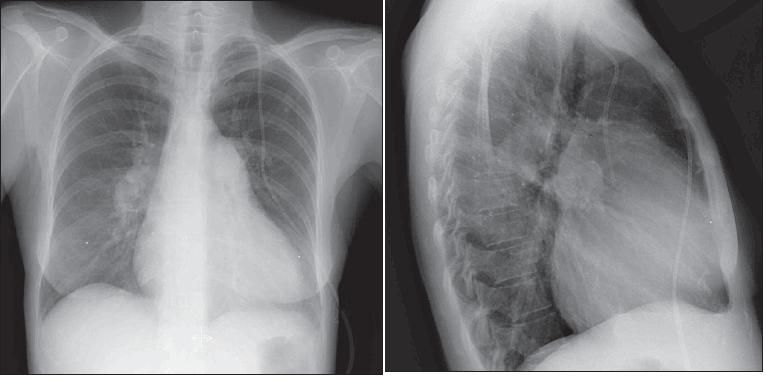

Radiographic evidence of longstanding PH includes enlargement of the central pulmonary arteries with abrupt narrowing of the more distal branches, giving a "prunedtree appearance," and RV enlargement (Figure 4).19 The classic radiographic changes characteristic of RV enlargement include increased transverse diameter of the heart, elevation of the cardiac border on the posteroanterior view, and narrowing or loss of the retrosternal airspace on the lateral projection. All or some of these findings can be found in patients with IPAH but lack sensitivity for the diagnosis. Also, there is no correlation between the extent of these abnormalities and the degree of PH.20

Figure 4 – Cardiomegaly and prominent bilateral pulmonary arteries in the hilar areas can be seen in the posteroanterior chest radiograph from a patient with idiopathic pulmonary arterial hypertension. The lateral view also reveals enlarged pulmonary arteries and cardiomegaly without any evidence of congestive heart failure.